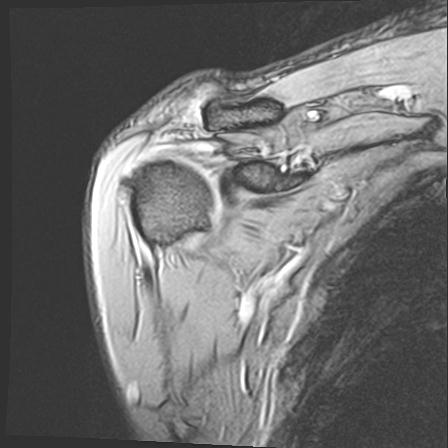

60058 3/9 11/4 右肩 2R+MRI 73歳男性 肩腱板損傷